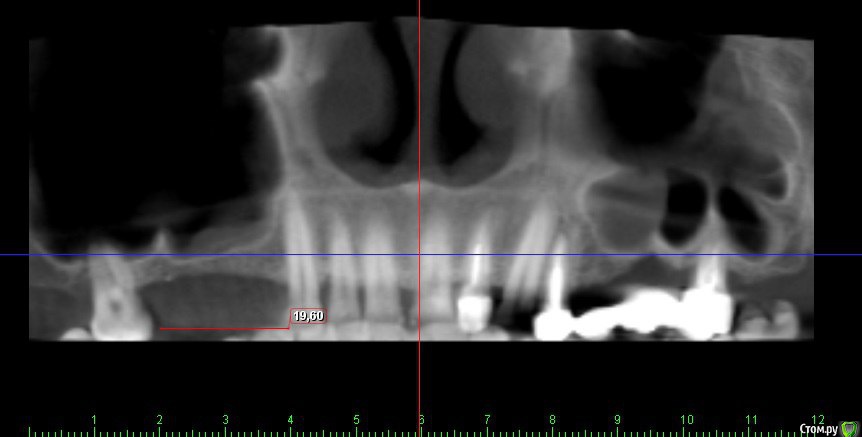

Kovalov Igor Опубликовано 19 мая, 2016 Поделиться Опубликовано 19 мая, 2016 (изменено) Здравствуйте уважаемые форумчане! Нужен совет по повторному синуслифтингу....3 месяца назад проводилась попытка синуслифтинга в 1 сегменте, отсутствие 14,15,16 зубов ... Разрез, формирование окна, в этом случае выбрал вход в синус с двух окон в проекции 14 и 16, получить перфу возле септы в области 16 когда отслаивал ... 14 отслойка без проблем... закрыл окна мембраной и ушил отправил погулять на 2,5-3 месяца.Вопрос как поступить ? Сделать одно большое окно? Как быть со спайками и как сложно их отделять ? Мембрану под перфу не подложил так как не делал ниразу этого... Кт после 3х месяцев ... Изменено 19 мая, 2016 пользователем Kovalov Igor Ссылка на комментарий

kriokov Опубликовано 19 мая, 2016 Поделиться Опубликовано 19 мая, 2016 пошел бы стандартно одним окном, да и первый раз думаю надо было одним окном идти, там не полная септа.Иногда приходиться остро работать на спайках как при расщеплении. Не знаю, но мне здесь одно здоровое окно видиться. И наверное зря Вы септу не спилили или не выкусили при первом заходе, если решили через три мес на повторный идти. Синус не плохо выглядит, думаю нормально все будет. 6 Ссылка на комментарий

kriokov Опубликовано 20 мая, 2016 Поделиться Опубликовано 20 мая, 2016 1 грамма мало на такой синус' даже крупного. 1,5 - 2 гр думаю 4 Ссылка на комментарий

red_butler Опубликовано 21 мая, 2016 Поделиться Опубликовано 21 мая, 2016 Куда вы 2гр L сыпите та? Тромбуете штоль?Даже еще раз пересмотрел срезы, Вы считаете что на такой операционной площади и при таком строении синуса расход будет меньше? 3 Ссылка на комментарий

Kovalov Igor Опубликовано 21 мая, 2016 Автор Поделиться Опубликовано 21 мая, 2016 Даже еще раз пересмотрел срезы, Вы считаете что на такой операционной площади и при таком строении синуса расход будет меньше?Ушло 2 грамма вы правы! ))) Спасибо всем за советы , ошибки были в первом случае малое и высоко расположенное окно, сделал в этот раз одно большое окно, спайки были только по периметру окна , было ощущение что окно начало заростать костью через три месяца, будто пластинка была поверх мембраны , может показалось ...Отслаивал до септы, графт 1,5 гр. в синус и 0,5 латерально от винтов и укрыл мембраной 25*25 владмива, мембрана не понравилась если честно ) Ссылка на комментарий